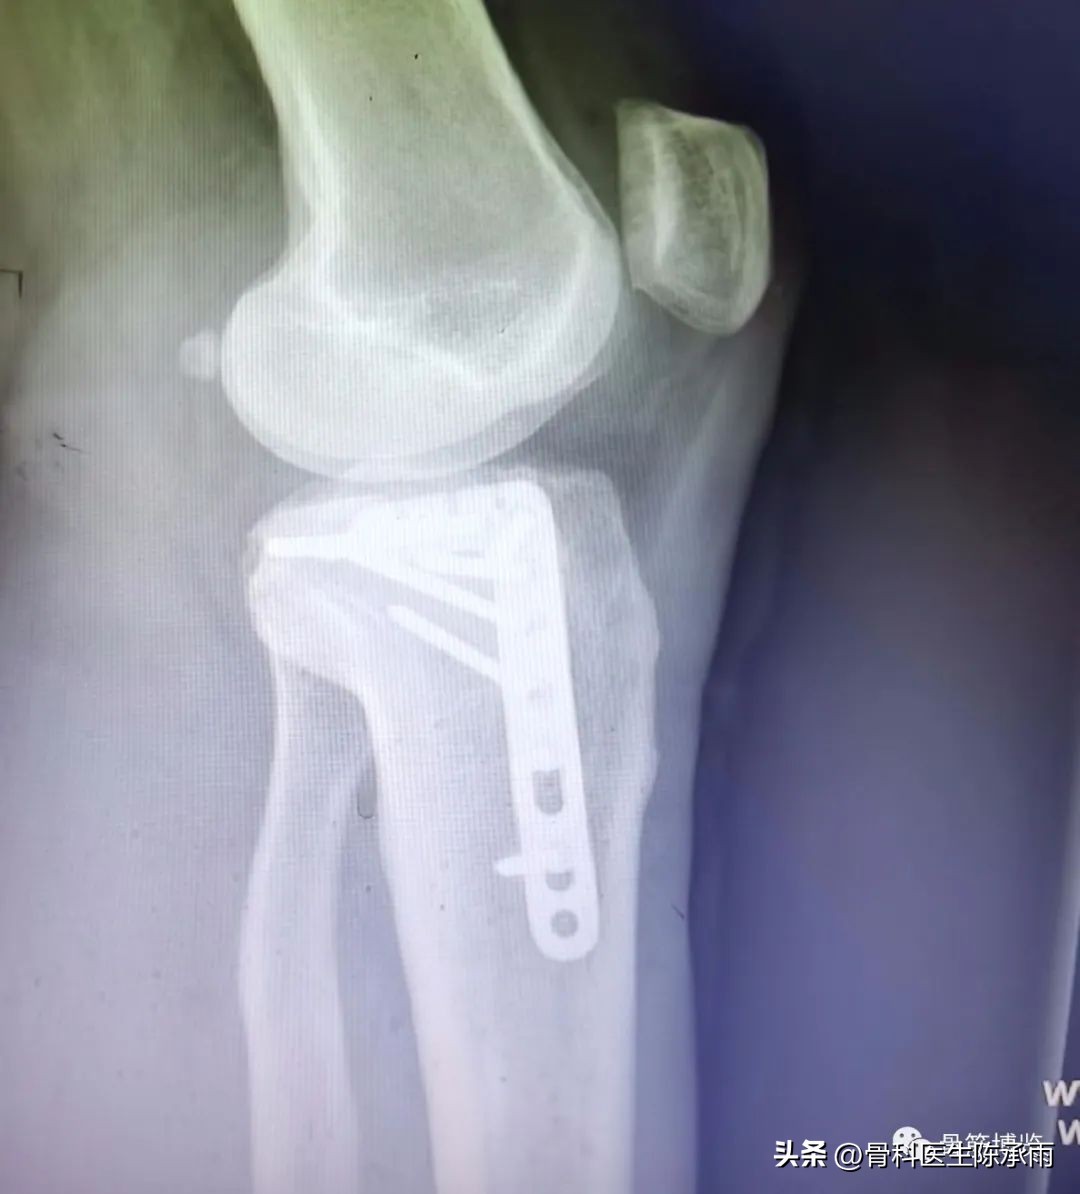

1例

2例

3例

4例

5例

6例

7例